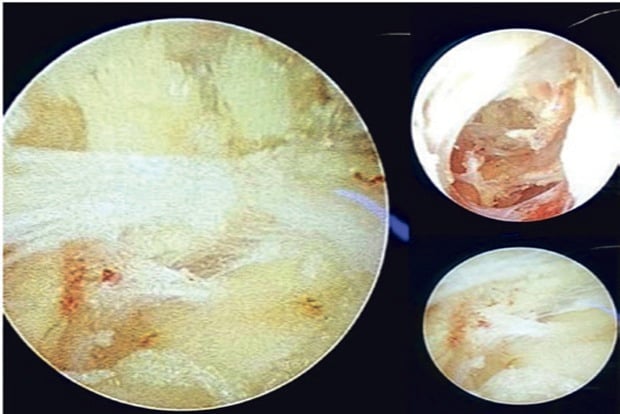

Screengrab of the fistulous tract

With these in mind, the surgeon at the SRM Medical College Hospital and Research Centre (SRM MCH and RC) in Kattankulathur have attempted to do a Video Assisted Anal Fistula Treatment (VAAFT) for patients.This novel technique, developed in 2006, is gaining popularity all around the world. SRM’s first patient was a 25-year-old male who came to the OPD with complaints of perianal discharge. Investigations were done which confirmed the diagnosis of fistula-in-ano. He was successfully treated with VAAFT and was discharged the next day as he had minimal post-operative pain, there was no open wound and there were no major complaints.